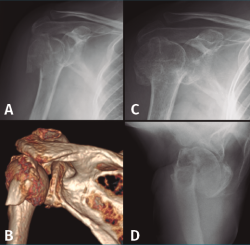

En el grupo que estamos analizando de pacientes en edad laboral con fractura compleja de húmero proximal su aplicación es limitada. Solamente quedaría indicado probablemente en pacientes mujeres mayores de 60 años con fracturas de 3 o 4 partes no muy desplazadas, con mala calidad ósea, un trabajo sin grandes requerimientos físicos y una vida extralaboral no muy activa (Figura 2). En estos pacientes la inmovilización con un cabestrillo de 4-6 semanas y la posterior rehabilitación funcional constituyen el tratamiento habitual.

Figura 2. Evolución radiológica del tratamiento conservador de una fractura de húmero proximal derecho. A: radiología simple anteroposterior; B: reconstrucción de la tomografía computarizada de la fractura de 4 partes desplazada; C y D: evolución radiológica del tratamiento conservador.

La HA en pacientes en edad laboral es también una opción de rescate ante un fracaso de osteosíntesis o tras una osteonecrosis (Figura 4). Hoy en día podemos encontrar artroplastias modulares que son reconvertibles si fuera necesario a una prótesis invertida sin tener que retirar el vástago. - Prótesis invertidas (RSA). Vistos los resultados no del todo satisfactorios de las HA por la no consolidación de las tuberosidades, se empezaron a colocar RSA en pacientes mayores con fracturas desplazadas, sobre todo en el contexto de roturas del manguito. Con estas prótesis se consigue buenos resultados en cuanto a dolor y una movilidad satisfactoria en pacientes con pocas demandas funcionales. La RSA es una intervención agresiva que deja menos stock óseo en caso de necesitar una revisión. En nuestro grupo de pacientes en edad laboral es muy infrecuente necesitar de entrada resolver una fractura de húmero proximal con una RSA, pero es una opción que tenemos que tener en cuenta. Se han desarrollado también implantes con minivástagos o de apoyo metafisario que permitirían menor pérdida de stock óseo y una revisión menos complicada si fuera necesario.

Figura 4. Evolución radiológica de una osteosíntesis de una fractura de húmero proximal izquierdo. A: radiología preoperatoria; B: osteosíntesis con placa; C: fallo en varo de la osteosíntesis; D: implantación de una hemiartroplastia.